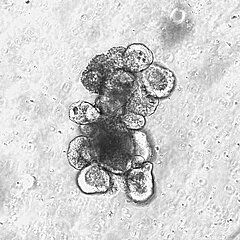

Patienten, die Tumortherapien wie Bestrahlung oder Stammzelltransplantationen erhalten, leiden häufig unter schweren Schädigungen der Darmschleimhaut. Sie leiden nicht nur unter den Schmerzen und Komplikationen, sondern haben auch langfristig schlechtere Behandlungsergebnisse. Eine Studie der LIT-Kooperationsgruppe „Innate Immunstimulation bei Krebs und Transplantationen" im Journal „Nature Communications“ zeigt, wie ein bakterielles Stoffwechselprodukt die Darmbarriere schützt und die Regeneration der Darmschleimhaut durch Stammzellen fördert. Die Ergebnisse verdeutlichen zudem, dass das mikrobielle Produkt auch die Immunabwehr gegen Leukämie stärkt.